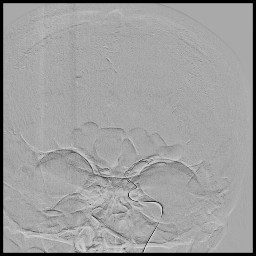

9. EVAR

EVAR stands for Endovascular Aneurysm Repair.

EVAR Endovascular Aneurysm Repair) for an abdominal aortic aneurysm.

3D reconstructed images of infrarenal abdominal aortic aneurysm (AAA) before (A & B) and after (C, D & E) endovascular aneurysm repair. Imaginary contour of the original aortic wall (orange dotted line).

10. BEVAR

BEVAR stands for  Branch Endovascular Aneurysm Repair

BEVAR Branched Endovascular Aortic Repair

Emergency branched endovascular aortic repair for ruptured aortic psuedoaneurysm (A, blue arrow) secondary to osteophyte compression. 3D reconstruction of pre (A & B) and post (C, D & E) BEVAR of all four vessels (Celiac, SMA and both renals). There was severe stenosis of the left common iliac artery which was also stented (B and D, blue arrow). F and G depicts the substracted images to demonstrate main stent graft body-branches structure.